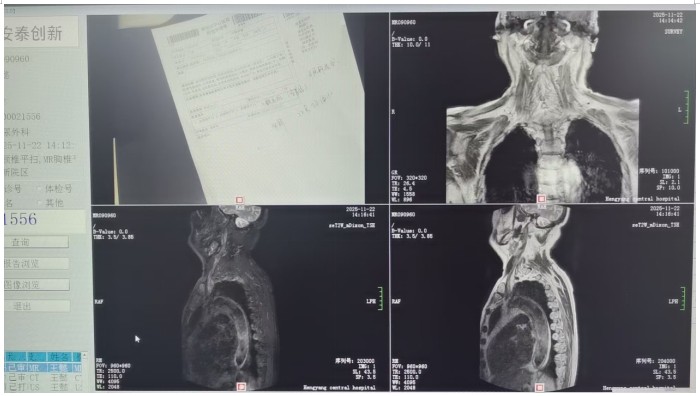

衡陽市中心醫(yī)院馬子芳團(tuán)隊(duì)助力八旬老人重獲排尿自由 發(fā)布時間:2026年01月10日 10:55:41 預(yù)覽:903次 通訊員殷君發(fā)報(bào)道:近日,衡陽市中心醫(yī)院泌尿外科馬子芳主任醫(yī)師團(tuán)隊(duì)成功為一名82歲高齡的神經(jīng)源性膀胱男性患者實(shí)施院內(nèi)首例骶神經(jīng)刺激器植入術(shù),幫助老人重獲“排尿自由”,標(biāo)志著衡陽市中心醫(yī)院在功能性泌尿疾病診療領(lǐng)域邁上新臺階,為受排尿困難困擾的患者帶來了新希望。該老人入院前1個月無明顯誘因開始出現(xiàn)排尿困難,加重3天。主要表現(xiàn)為排尿費(fèi)力、排尿等待、尿末滴瀝、尿線變細(xì),伴夜尿增多,嚴(yán)重影響睡眠質(zhì)量與日常生活,患者和家人都備受煎熬。老人同時患有椎基底動脈綜合征(后循環(huán)缺血)、高血壓病3級、腔隙性腦梗死、雙側(cè)頸動脈多發(fā)斑塊形成、前列腺術(shù)后等多重疾病。為進(jìn)一步治療,患者到衡陽市中心醫(yī)院泌尿外科就診。 馬子芳團(tuán)隊(duì)詳細(xì)詢問患者病史和治療情況后,對患者進(jìn)行了相關(guān)輔助檢查,初步診斷患者為神經(jīng)源性膀胱??紤]到老人82歲高齡、基礎(chǔ)疾病多等情況,團(tuán)隊(duì)多次組織病例討論,與患者及家屬充分溝通,最終決定為患者實(shí)施微創(chuàng)、可逆的骶神經(jīng)刺激器植入術(shù)進(jìn)行治療。很快,馬子芳團(tuán)隊(duì)為老人實(shí)施了一期骶神經(jīng)調(diào)控電極植入術(shù),術(shù)中精準(zhǔn)定位,成功穿刺骶3神經(jīng)孔,術(shù)中測試各位點(diǎn)的運(yùn)動應(yīng)答、感覺應(yīng)答明顯,無不良反應(yīng)。 經(jīng)過約3周的體驗(yàn)治療期后,老人來醫(yī)院復(fù)查,尿頻、尿急、尿痛、排尿困難較術(shù)前好轉(zhuǎn),無紅腫,電極及導(dǎo)線無移位。基于患者意愿和一期術(shù)后良好療效,馬子芳團(tuán)隊(duì)決定為老人施行二期骶神經(jīng)刺激器永久植入術(shù)。二期骶神經(jīng)刺激器永久植入術(shù)后,患者術(shù)后恢復(fù)良好,尿頻、尿急、尿痛、排尿困難等癥狀明顯改善,生活質(zhì)量大幅提升。術(shù)后隨訪時,患者欣喜地說道:“現(xiàn)在我可以一覺睡到天亮了,感覺整個人都精神了!”馬子芳主任醫(yī)師介紹,骶神經(jīng)調(diào)控療法手術(shù)微創(chuàng)、可逆、可調(diào)節(jié)、可實(shí)現(xiàn)對患者的精準(zhǔn)治療,現(xiàn)已被廣泛應(yīng)用于治療各種下尿路功能障礙疾病,如尿頻、尿急、急迫性尿失禁、排尿困難、非梗阻性尿潴留、大便失禁等,并創(chuàng)新性地應(yīng)用于盆底疼痛綜合征、便秘等盆腔功能障礙性疾病的治療,“此次為高齡患者成功實(shí)施骶神經(jīng)調(diào)控術(shù),這不僅考驗(yàn)團(tuán)隊(duì)的技術(shù)實(shí)力,也是醫(yī)院精準(zhǔn)醫(yī)療、人文醫(yī)療理念的生動體現(xiàn),開啟了衡陽地區(qū)排尿功能障礙診療的新篇章,體現(xiàn)了衡陽市中心醫(yī)院以患者為中心的理念。”